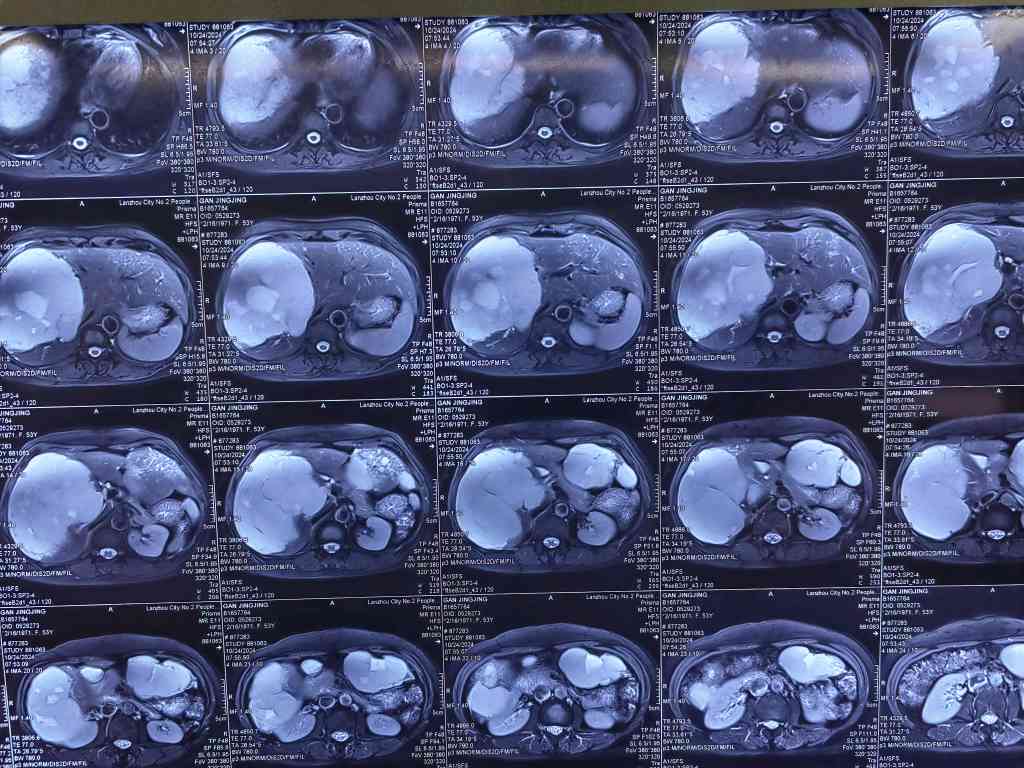

1. **手术适应症**:成人巨大肝血管瘤,通常指直径在10-15cm甚至大于15cm的血管瘤。对于这类血管瘤,如果引起压迫症状、存在出血风险,或者引发凝血功能异常,一般建议进行外科手术治疗。特别是对于年轻女性,由于肝血管瘤可能随时间发展,对肝脏功能产生较大影响,因此更建议采取积极手术治疗 。

3. **手术风险与处理**:巨大肝血管瘤手术风险较大,特别是出血问题。因此,控制出血是手术中的一个重要环节。术前可考虑进行肝动脉栓塞治疗,以缩小肝脏体积,提高手术安全性。肝动脉栓塞还可以使血管瘤硬化,有助于保障手术安全 。